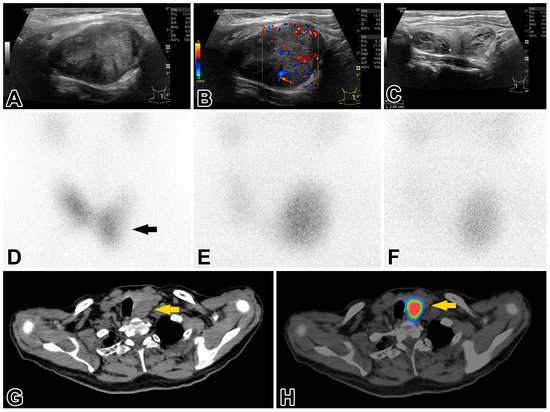

2.2. Investigations of the Thyroid and Parathyroid Gland